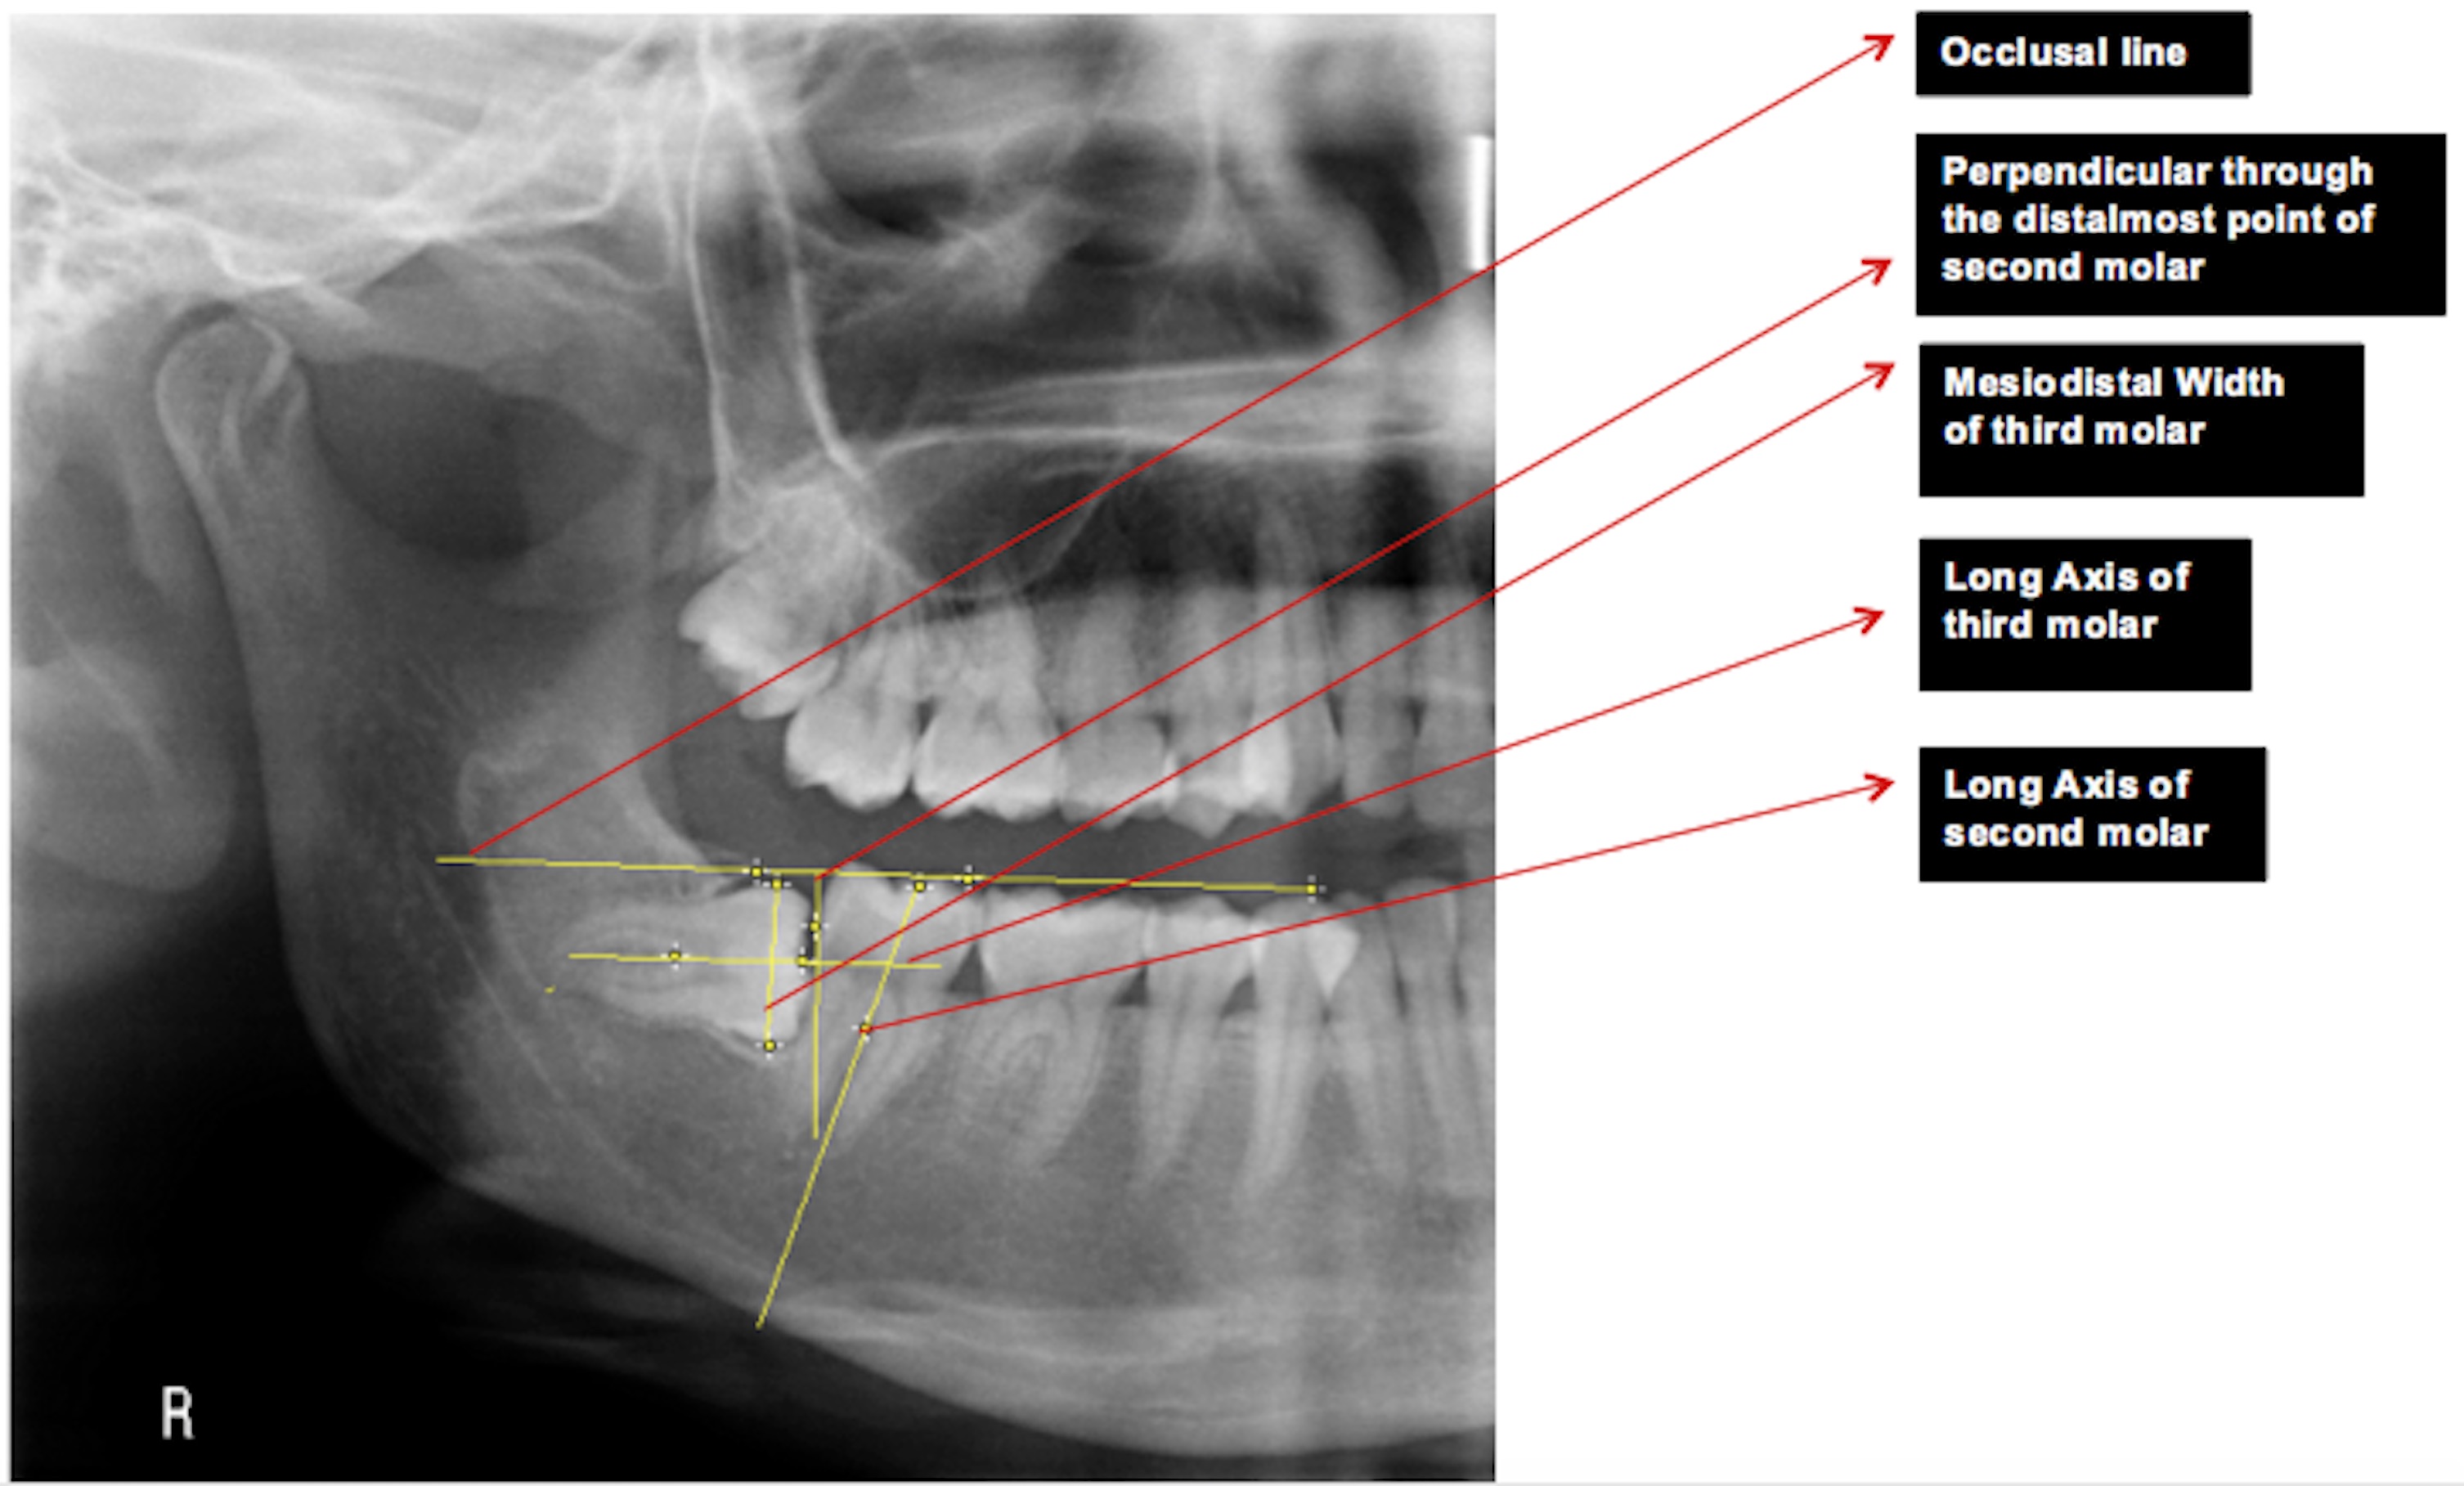

Materials & Methods: Total of 220 patients’ M3Ms (i.e 440 sites of M3Ms) were assessed with Panoramic Radiographs, in Department of Oral Medicine and Radiology. The impaction status was divided as class of impaction (I, II, III), level of eruption (A, B, C) and angulation (mesioangular, vertical, distoangular and horizontal). Data were entered in Microsoft excel sheet and analyzed using SPSS software version 11.5. Results: Class II impaction state was

most commonly present in this population group, in 345 sites (85.18%) while none of the patients had class III impaction. Level A eruption was most prevalent, 315 sites (77.78%). The least prevalent was level C eruption, 14 sites (3.46%). Majority 18 sites (46.67%) had vertical inclination while only 32 sites (7.9%) had horizontal inclination.

Conclusion: The most prevalent impaction state of M3M in this population

group is Class II, Level A with vertical angulation.